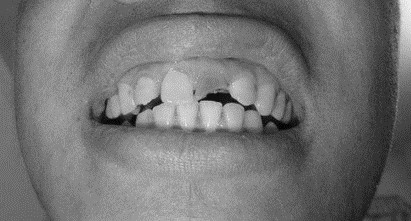

患者,男,38歲。上前牙變色1年,自述上前牙5年前受過外傷,唇側(cè)傾斜,檢查可見左上1牙冠變色,牙冠缺損近1/2,牙髓測試無反應(yīng),X線根尖片顯示患牙無明顯異常,全景片顯示雙側(cè)下頜智齒近中阻生,之前有發(fā)炎化膿病史,目前無咀嚼不適。口腔其余無異常。

檢查情況及X線片見下圖:

(1)上前牙變色1年,上前牙5年前受過外傷,唇傾明顯。

(2)檢查見左上1牙冠變色,牙髓測試無反應(yīng),牙冠缺損近1/2,X線片無明顯異常。